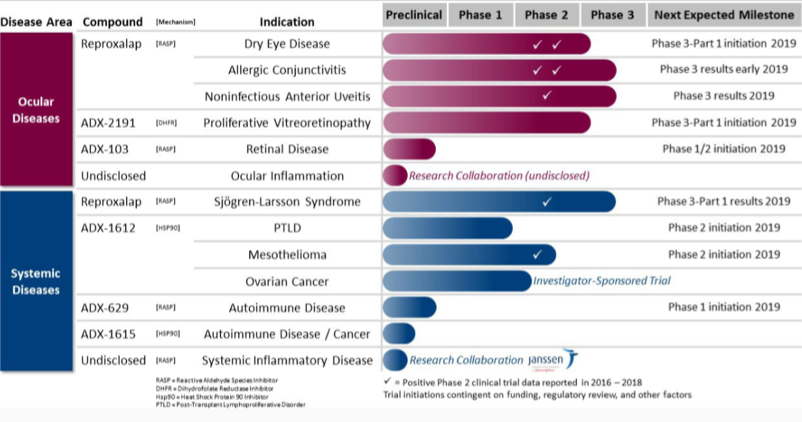

Aldeyra’s lead product candidate is reproxalap, a small molecule RASP (Reactive Aldehyde Species) inhibitor that can be used in the treatment of dry eye disease, allergic conjunctivitis, noninfectious anterior uveitis, and Sjögren-Larsson Syndrome. It is also developing other drug candidates for cancer, autoimmune diseases, post-transplant lymphoproliferative disease and retinal inflammation.

Image Source: Company

In the pipeline are drug candidates ADX-1612 for Mesothelioma, PTLD and Ovarian cancer, ADX-629 and ADX-1615 for autoimmune disorders that are undergoing clinical trials. It announced positive top-line results from its Phase I/II clinical trials for ADX-1612 (ganetespib) in patients with pleural malignant mesothelioma named MESO-2, which showed improved partial response rates when combined with standard pemetrexed and platinum therapy. It is in preparation of phase II trials pending its discussion with regulatory authorities.

As per the company’s press release, “The MESO-2 results are highly encouraging. Addition of ADX-1612 to pemetrexed and either cisplatin or carboplatin achieved an overall response rate of 61%, the highest seen to date for addition of a novel agent to front-line chemotherapy,” said Professor Dean Fennell MD PhD, Chief Investigator of the Cancer Research UK MESO-2 clinical trial. “Hsp90 inhibition could represent a new advance for the treatment of mesothelioma.”

It raised funds amounting to $67.6 million through its underwritten public offering in October 2018. As of September 2018, its cash, cash equivalents, and marketable securities balance stood at $35.1 million.